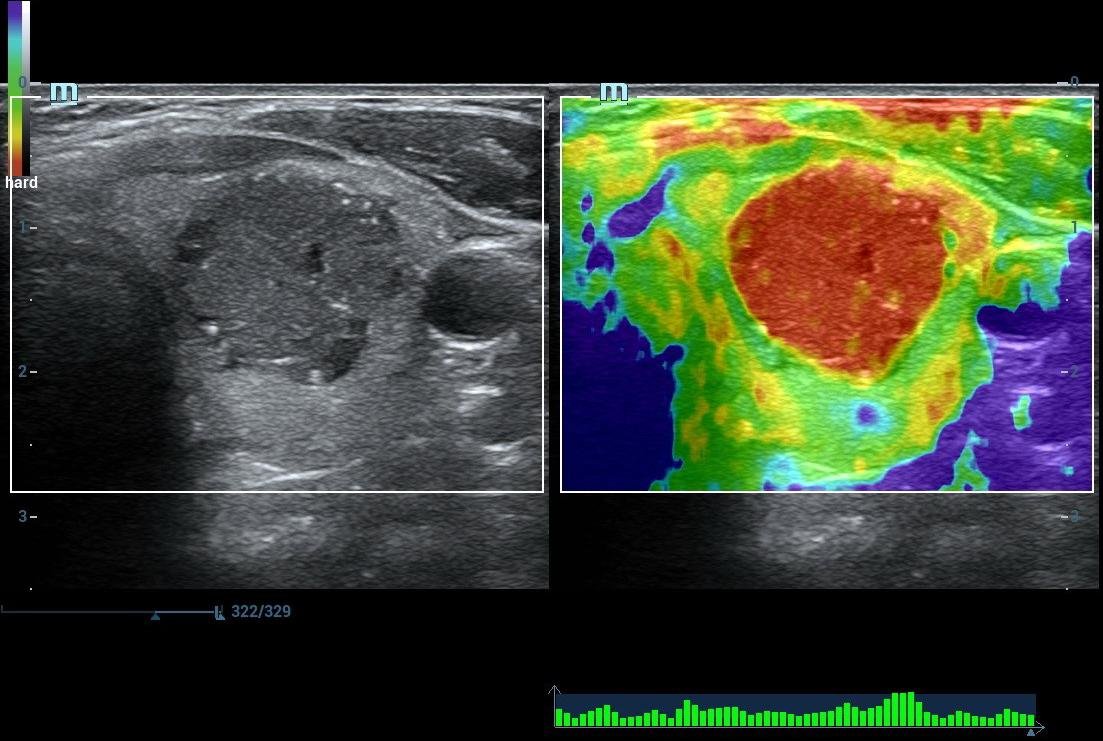

• Shear Wave Elastograghy & Strain Elastography

• High End SHEAR WAVE ELASTOGRAPHY For LIVER FIBROSIS/THYROID MALIGNANCY/BREAST CANCER